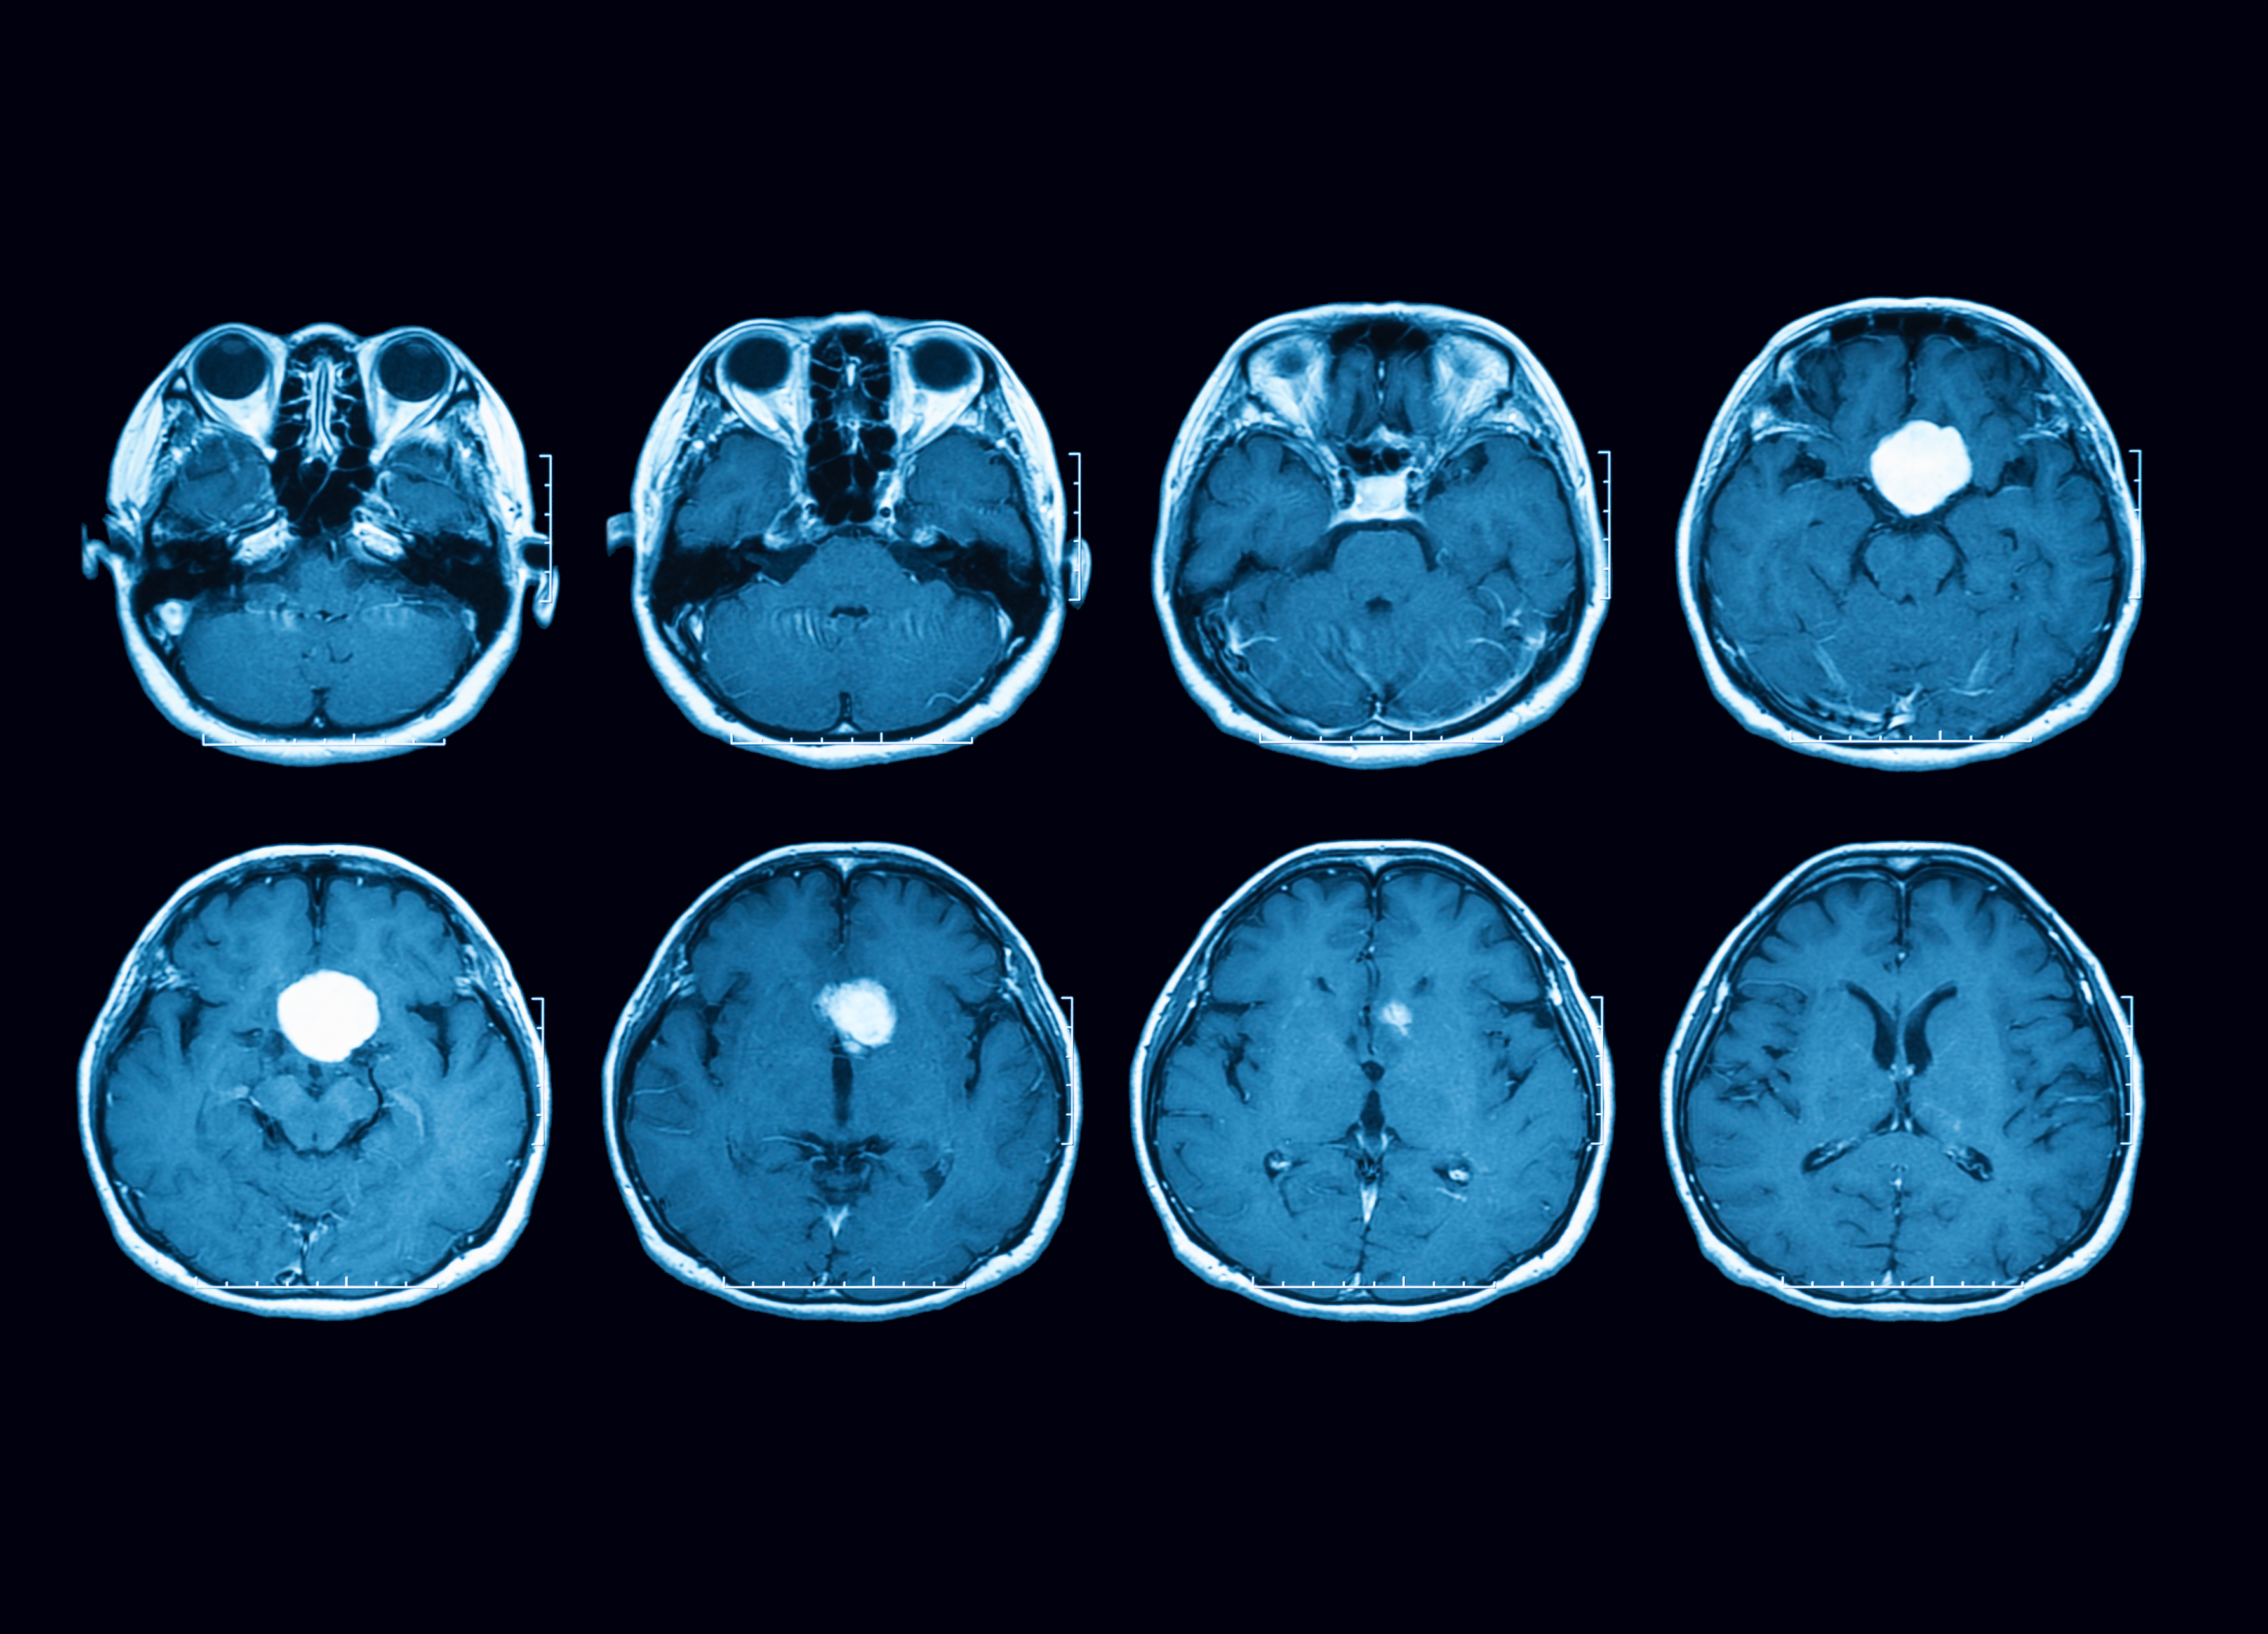

O diagnóstico começa com avaliação clínica e exames de sangue para medir os hormônios produzidos pela hipófise. Depois, a ressonância magnética da região da glândula permite visualizar o tumor e seu tamanho.

Tumores com menos de 1 cm são chamados de microadenomas; acima desse tamanho, macroadenomas. O porte e o tipo do tumor ajudam a decidir o tratamento mais adequado.